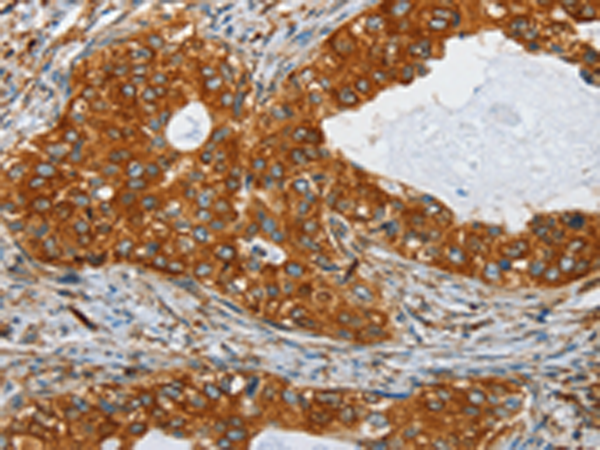

分类: 科研抗体货号: P07114别名: MSF; MSF1; NAPB; SEPT9; SINT1; PNUTL4; SeptD1; AF17q25应用: IHC反应种属: Human, Mouse, Rat